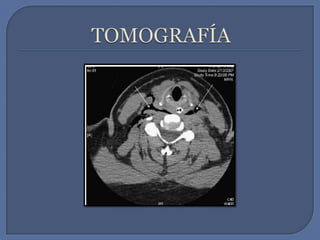

TOMOGRAFÍA